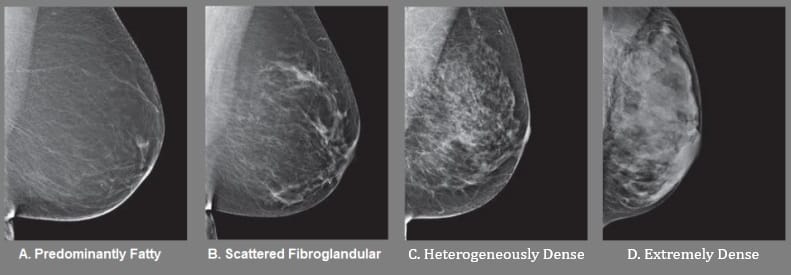

WHAT ARE THE BREAST DENSITY CATEGORIES?

- Predominantly fatty (0-25% Fibroglandular) indicates that the breasts are almost entirely composed of fat. About 1 in 10 women have this result.

- Scattered areas of fibroglandular density (26-50% Fibroglandular) indicates there are some scattered areas of density, but the majority of the breast tissue is fatty. About 4 in 10 women have this result.

- Heterogeneously dense (51-75% Fibroglandular) indicates that there are some areas of fatty tissue, but that the majority of the breast tissue is fibrous or glandular. About 4 in 10 women have this result.

- Extremely dense (76-100% Fibroglandular) indicates that nearly all of the breast tissue is fibrous or glandular. About 1 in 10 women have this result.

If it is determined you have dense breast tissue (Category C or D, or more than 50% Fibroglandular), even if the report indicates no signs of cancer were seen, it is important to know that the nature of dense breast tissue may make it more difficult to see early stages of cancer. Fibrous and glandular tissue appear white on a mammogram, as do some breast masses and cancers, which can be camouflaged by your natural tissue. In contrast, fatty tissue appears almost black on a mammogram, so it’s easier to see a tumor that looks white if most of the breast is more fatty.